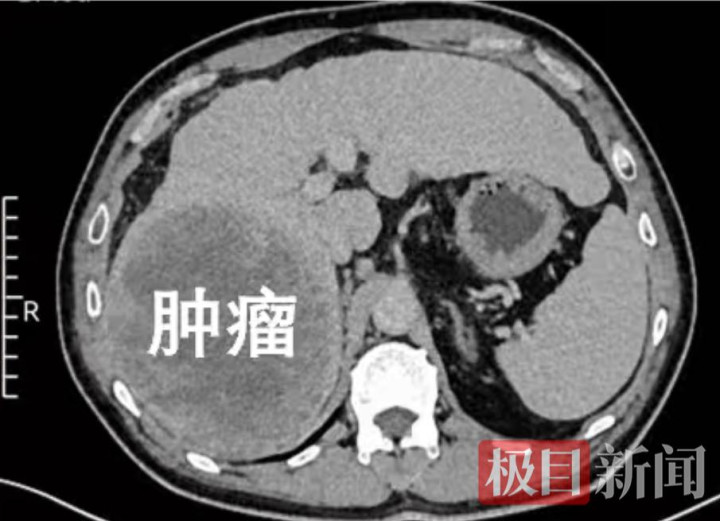

本年以来,吴先生时时感到肝脏不适,到武汉市第六病院就医搜检,影像走漏夸耀:肝右叶长有一个直径达14厘米的原发性肿瘤。万幸的是,肿瘤仅局限于肝脏右半部分,未发生全身扩散,且吴先生肝功能气象邃密,为手术诊治争取到了珍爱契机。

患者肝脏上的巨型肿瘤。